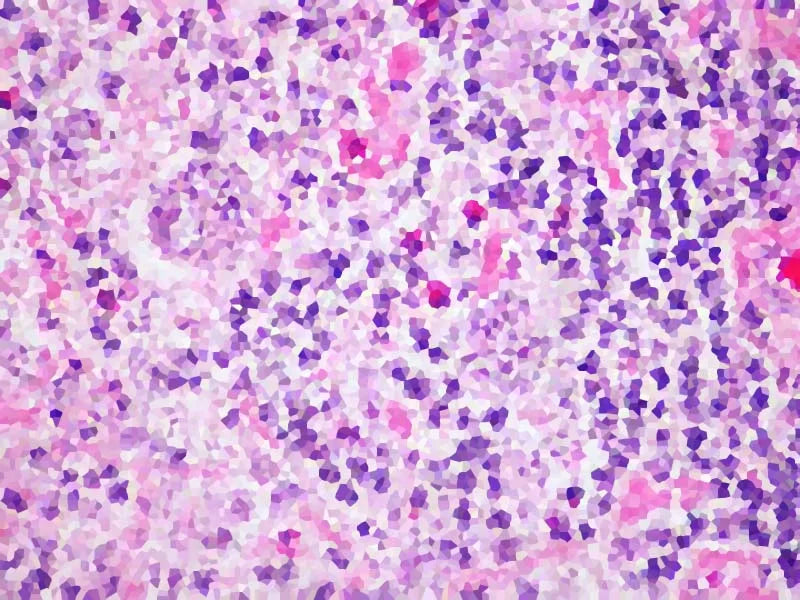

Quest’ultima patologia consiste nell’infiammazione delle fibre nervose e delle cellule deputate alla produzione della mielina (la “guaina” che avvolge tali fibre). La progressiva lesione e perdita della mielina causa l’insorgenza di placche che aggrediscono il sistema nervoso centrale; si passa da uno stadio iniziale infiammatorio alla formazione di vere e proprie cicatrici (appunto, le sclerosi). Si tratta di una malattia cronica (neurodegenerativa) scatenata dall’alterazione del sistema immunitario, che è il responsabile dell’infiammazione.